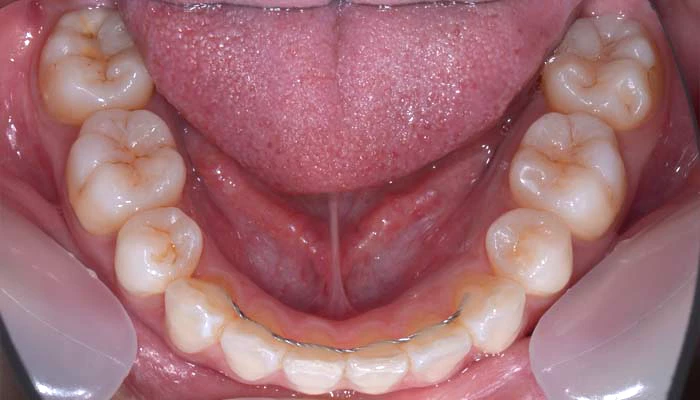

治療例15. 下の歯のガタツキを治したい

治療前

経過

治療後

主訴 | 下の歯のガタツキを治したい |

---|---|

治療期間 | 10ヶ月 |

治療費 | 35万+tax (別途調整料) |

治療内容 | 下顎リンガル矯正(裏側矯正) |

治療のリスク | 後戻り |